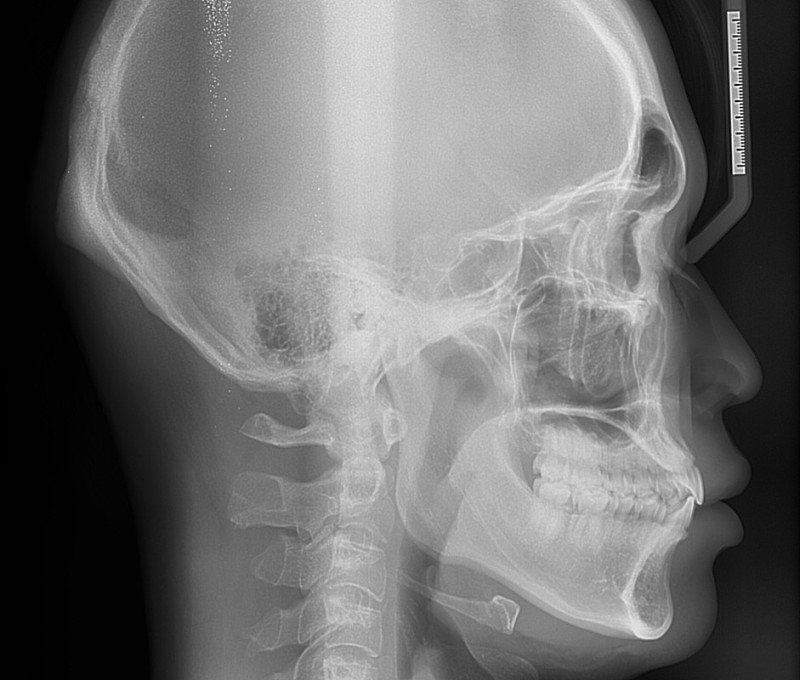

거북목인가요? 아님 그냥 하악턱이 돌출되어서 그런건가요?

평소에 그냥 편한자세로 걸어다니는데 주변에서 허리피고 턱내리고 걸으래요ㅠ

뭔가 제가 턱을 들고다니는것같기도 하고 아닌것같기도 해서 잘모르겠어요

질문1)거북목이면 턱도 들고다니나요?

질문2)턱이나와서 그렇게 보이는건지 아니면 거북목증상 있어서 그런건지 알수있을까요? 대략적으로라도요

허리피고 가슴피고 턱내리고 다니면 뒷목부근이 땡겨서 불편해요

턱의 문제보다는 고개를 들고 걷는 경향이 심한 것으로 보입니다.

턱은 일반적인 상태로 보입니다.

• 1. 거북목이 있다고 턱을 들고 다니지는 않습니다.

2. 올리신 옆모습 사진이나 두부의 x-ray 사진으로는 거북목 여부를 판단할 수 없습니다.